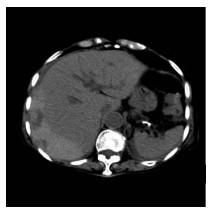

肝病超声诊断指南

中华医学会超声医学分会, 中国研究型医院学会肿瘤介入专业委员会, 国家卫生和健康委员会能力建设和继续教育中心超声医学专家委员会

2021, 37(8): 1770-1785. DOI: 10.3969/j.issn.1001-5256.2021.08.007

摘要(3068) HTML (6587) PDF (9311KB)(804)

超声检查无创、实时、价廉,无辐射、便于反复进行,是最常用的肝脏影像学检查方法。近年来,超声检查新技术如超声造影、弹性成像发展迅速,可有效鉴别肝内占位性病变性质、评估肝纤维化和门静脉高压程度以及监测肝病治疗效果,在临床肝病及其介入治疗中发挥重要诊断价值。本指南规范了肝病多模态超声技术(灰阶超声、彩色多普勒超声、超声造影、弹性超声)检查的仪器调置、患者准备及医生检查方法;对肝脏弥漫性病变(炎性病变、纤维化、硬化)、多种占位性病变及肝病介入操作的多模态超声技术诊断标准进行了定义和规范,同时推荐了超声监测周期及肝脏疾病超声诊断报告书写规范。